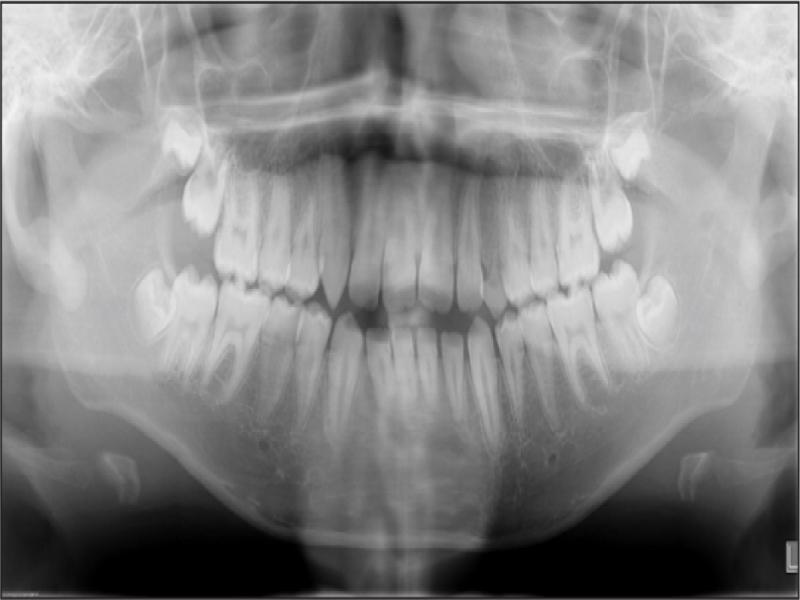

A 12-year-old African American male in good general health presented with the chief complaint of “I don’t like my upper front teeth”. An extra-oral examination revealed a convex soft tissue profile, an obtuse nasolabial angle, and lips that were protruded and incompetent. Upon intraoral examination, the patient had tooth staining, a retained deciduous upper left canine, a malformed upper right canine, a Class I molar relationship, spacing, an increased overjet and an anterior open bite (Figure 1). A radiographic examination revealed a congenitally missing upper left canine, an upper right permanent canine with a long root, an upper right first premolar with a short root, proclined and protruded upper and lower incisors and a high mandibular plane angle (Figures 2 and 3; Table I).

Panoramic radiograph taken at the initial visit (age 12 years, 0 months).